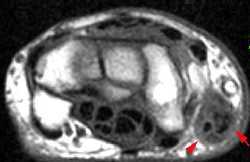

Explications avec une spécialiste. Mots clés : Douleur , Kyste, Cancer, Échographie, Sein. Elle correspondait à un cordon palpable cliniquement dans le quadrant supéro-externe du sein droit. Si vous avez mal au sein , plusieurs pistes sont à explorer.

Un maintien plus droit peut alors aider. Les changements fibrokystiques se caractérisent par une douleur , des kystes et un développement nodulaire généralisé dans le sein. Depuis quelques temps la partie inférieure de mon sein droit est douloureuse , des sensations de brûlures, de tension en permanence. A quoi peuvent correspondre les douleurs thoraciques ? Quelle est la cause de cette sensibilité des seins enceinte ? Ce phénomène peut même survenir en milieu .